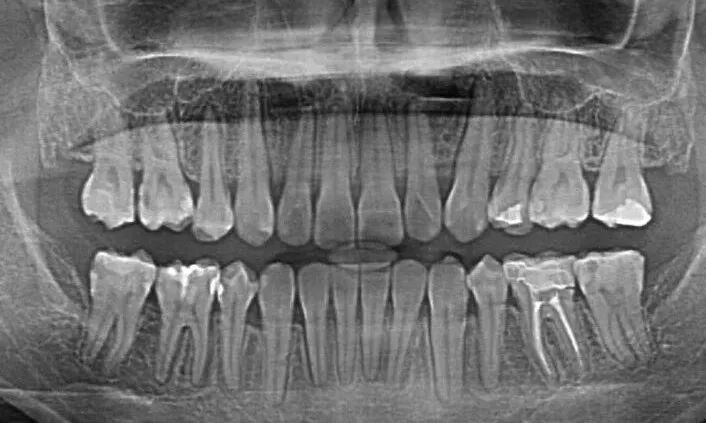

全口的曲面断层片:可以拍摄全口的所有牙齿以及关节区;可看到有无智齿、多生牙、根尖周炎、多少颗蛀牙等。

比如这张全景片,全口牙齿一般有 28-32颗,多出来的4颗就是智齿,智齿是从中间的牙齿往后数的第8颗,如果上下左右都有第8颗,那就是长了4颗智齿。

常见的蛀牙通常可以通过牙片发现,尤其是龋坏比较多的,在牙片上会出现黑色阴影的缺损。但如果是邻面龋,就需要到口腔机构,让医师用探针、口镜等进行检查确定。

一般正常情况下,牙齿周围是被牙龈包裹没有很大间隙的,即牙槽骨线为红色线标注位置。而图中牙槽骨那根线已经明显下降,且牙齿和牙齿之间有黑色阴影,说明有牙根暴露,牙槽骨吸收的情况,这种情况如不及时治疗就会引发牙齿脱落。

种植牙等修复体在口腔全景片上展现的通常是白色的,可以很清晰的看出来。另外补牙材料和金属或者全瓷牙冠也会显示出亮白色。